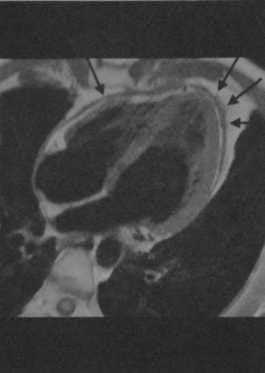

Острый перикардит у мужчины 37 лет. Т1 -взвешенная FSЕ-последовательность с темной кровью в четырехкамерном срезе демонстрирует выраженное утолщение и трудноопределяемый край перикарда (стрелки). Выпот в полость перикарда